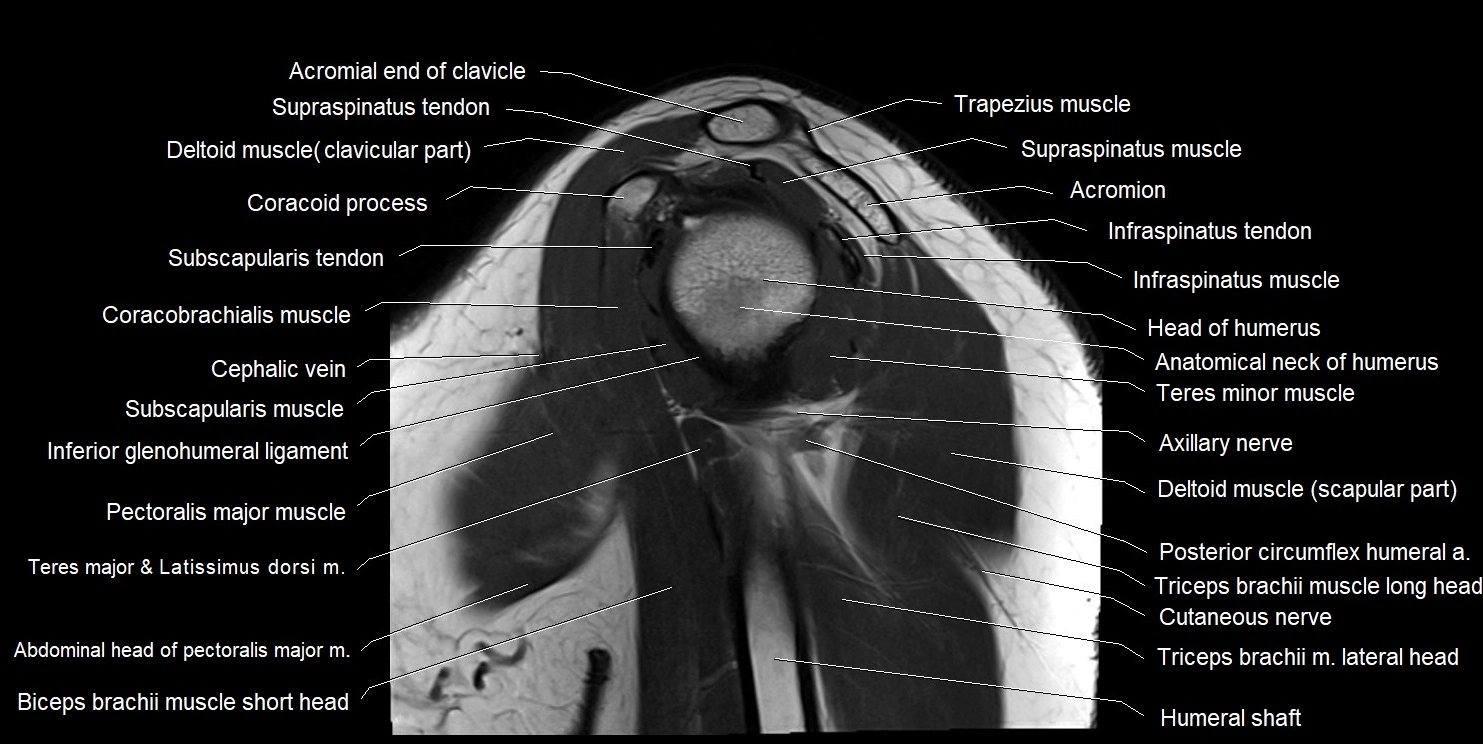

MRI images

image